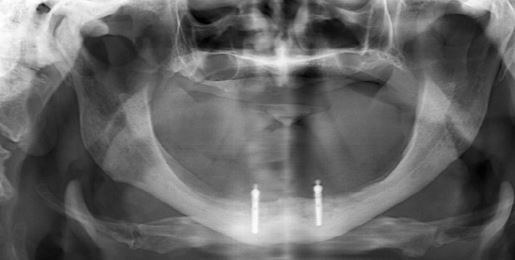

Dental İmplant Cerrahisi

Dikişsiz İmplant

Çene Implantasyonu

İmplant

İmplant Üstü Protezler